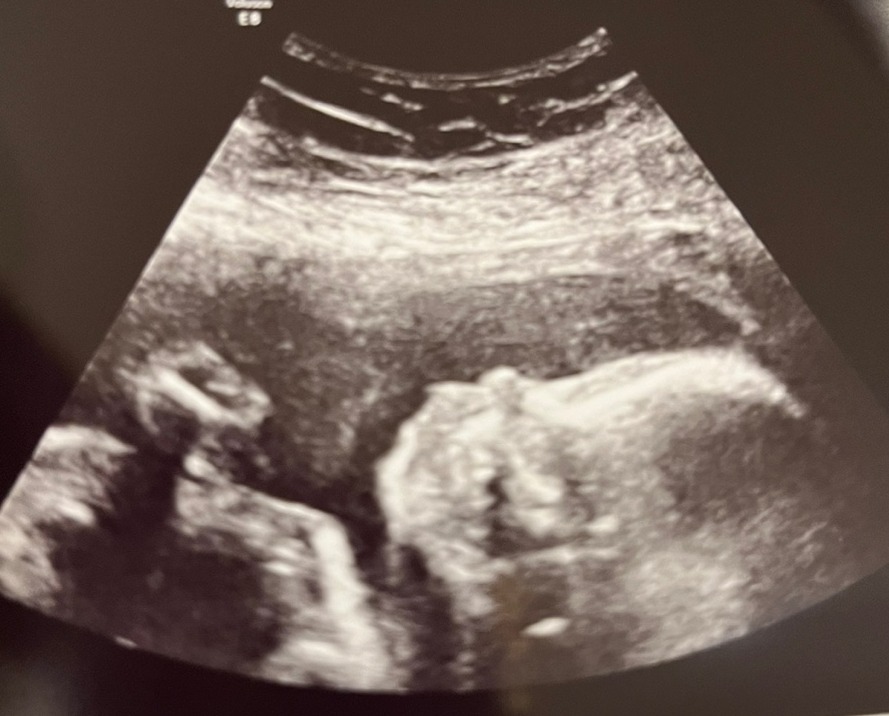

D-134일 (20주 6일차) 임신 중기 정밀초음파, 20주 정기 검진 본문

오늘은 부흥이가 21주를 맞이하기 하루 전 입니다.

오늘 병원에서 정밀초음파를 찍는 날이기도 합니다.

온다고 합니다. 5주만에 부흥이가 얼마나 컸는지,

잘 지내고 있었는지, 문제는 없는지 보러 가는 날이라서

기대도 되고 떨리고 설레는 날입니다.